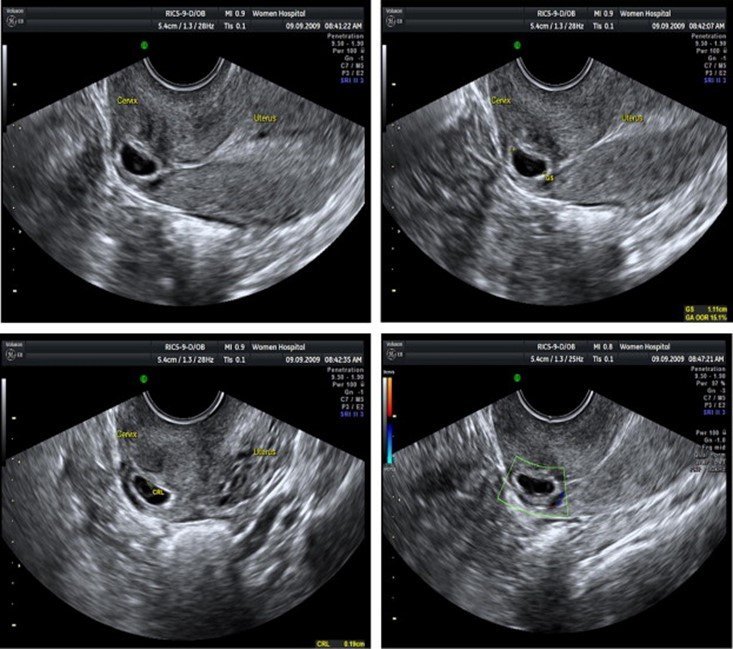

بارداری خارج از رحم چگونه تشخیص داده می شود؟

اگر علائم پارگی لوله فالوپ را ندارید اما پزشک متخصص زنان شما (دکتر زنان) مشکوک به بارداری خارج رحمی است، ممکن است:

-معاینه لگنی را انجام دهد

-برای اینکه ببینید محل دقیق بارداری خارج از رحم کجاست یک سونوگرافی واژینال انجام دهید.

-درخواست تست خون برای بررسی میزان هورمون بارداری به نام گنادوتروپین جفتی انسانی (hCG) حداقل در دو نوبت